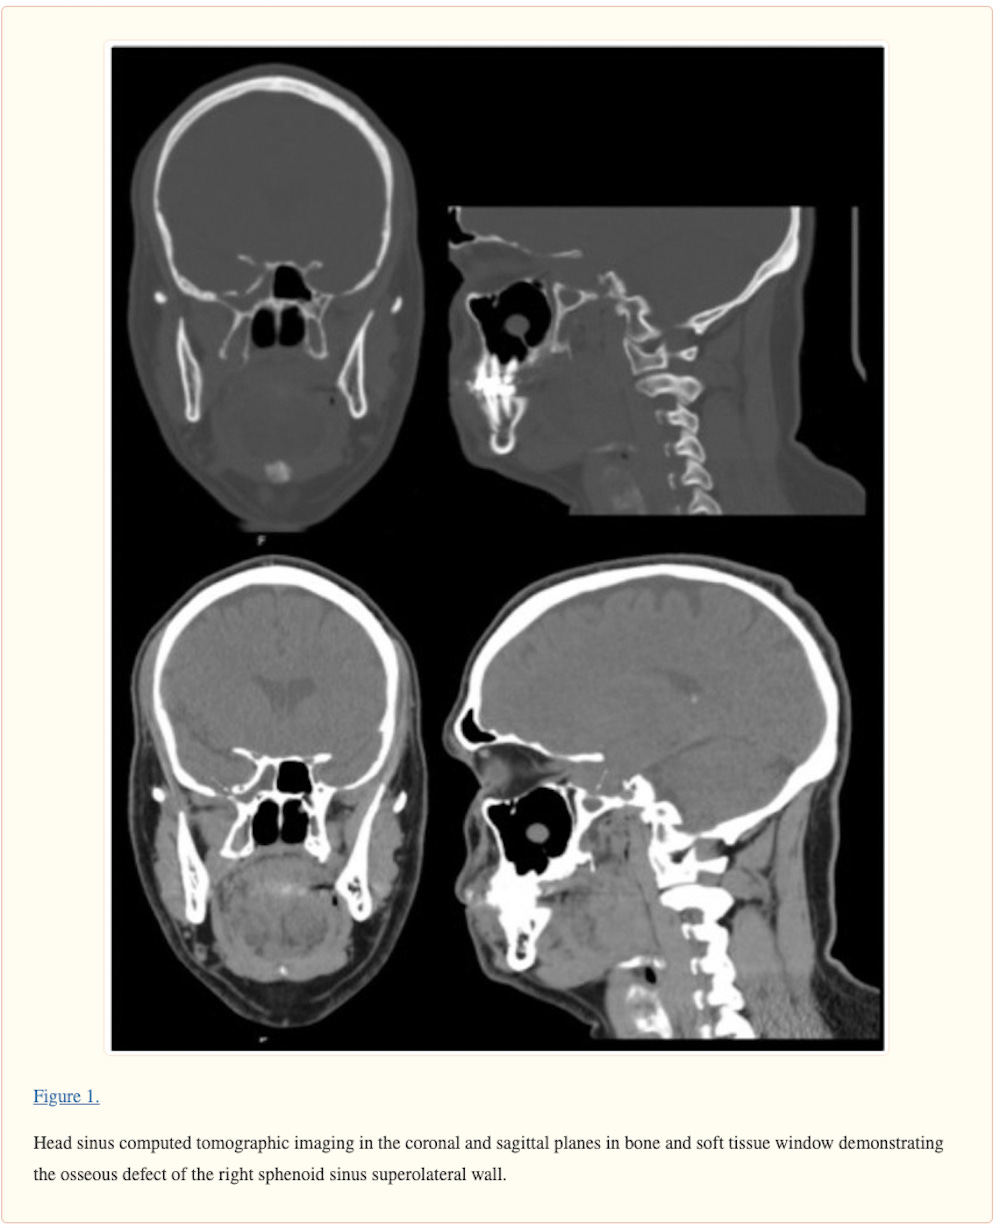

Cribriform Plate Injury After Nasal Swab Testing for COVID-19

An otherwise healthy man in his 40s presented for right-sided clear water rhinorrhea in December of 2020. Rhinorrhea originated after nasal swab testing and was mistakenly considered to be allergic rhinitis in the patient. The test was performed by a mobile unit at the patient’s home in March of 2020. The test was indicated because of previous contact with a woman who had a positive COVID-19 test result 5 days earlier. The patient had no symptoms of COVID-19 infection and RNA of SARS-CoV-2 was not detected by polymerase chain reaction (PCR) testing.

https://jamanetwork.com/journals/jamaotolaryngology/fullarticle/2784128

CT reveals shocking injury caused by COVID-19 nasal swab

The man, who had no previous injury to his skull and was otherwise healthy, underwent COVID-19 testing after being in contact with a woman who had tested positive for SARS-CoV-2. He had no COVID-19 symptoms, and his polymerase chain reaction (PCR) test result was negative.

An analysis of the patient's nasal discharge showed a high level of the beta-trace protein (23.7 mg/L) in the nasal secretion (normal range < 6 mg/L). The beta-trace protein test is a quick, noninvasive, and inexpensive method to detect CSF fluid in nasal secretions.

"Every instance of unilateral clear water rhinorrhea that appears after transnasal testing must be considered a potential CSF leak," the team wrote.

A 40-year-old man presented to the clinic for evaluation of CSF leak following COVID-19 testing via nasopharyngeal swab. During the swab, the patient reported feeling “something crack” upon deeper insertion of the swab and then had a large amount of clear rhinorrhea. Since the COVID-19 test, the patient had persistent clear fluid drain from the right side of his nose when tilting his head forward. The clear fluid was positive for beta-2 transferrin, and head computed tomographic imaging showed a small osseous defect in the superior and lateral wall of the right sphenoid sinus with opacification. The patient had resolution of CSF leak following repair of right skull base defect by an endoscopic transnasal/transsphenoidal approach with nasoseptal flap.